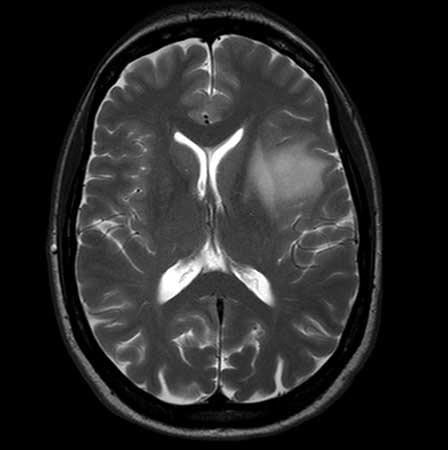

Advanced MRI Center

The Advanced MRI Center CORE facility provides the latest magnetic resonance imaging and spectroscopy capabilities to scientists, clinicians, government and industry, along with technical and clinical expertise for collaborative research.

The Center’s specialized techniques clarify functional, physiological and biochemical information from all organs of the body, enabling physicians to make more informed patient-care decisions. Additionally, researchers are better able to understand the mechanisms of such conditions as lung and heart disease, cancer, stroke, epilepsy, multiple sclerosis, lupus, rheumatoid arthritis, osteoarthritis, osteoporosis, back pain and injuries, autism, Alzheimer’s disease, bipolar disease and depression. This facilitates the development of new therapies that can be safely and continuously evaluated throughout patient treatment.

The Advanced MRI Center houses:

- 3T Philips Achieva whole-body scanner complete with a full array of clinical and animal RF coils